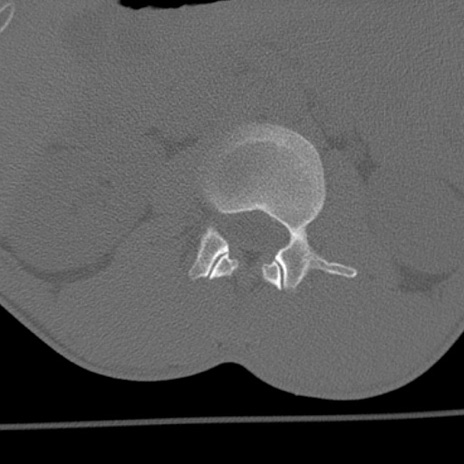

症例3 腰椎CT(横断像)

腰椎CT